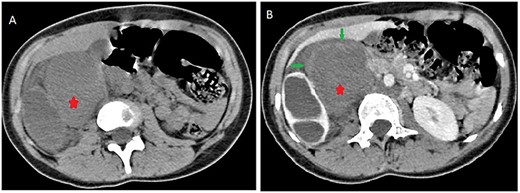

Contrast computed tomography (CT) scan revealed a voluminous (173 × 67 × 59 mm), well-limited and lobulated, right retroperitoneal tumor, hypodense, with delayed and low enhancement (Fig. 1).

Abdominal CT scan showing a retroperitoneal mass; retroperitoneal ganglioneuroma (red spark) before (A) and after (B) heterogeneous enhancement (green arrow).